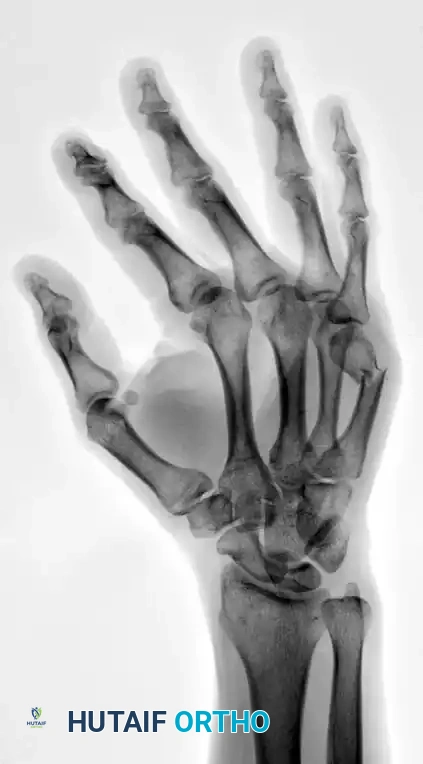

FIGURE 67-35B: Preoperative oblique radiograph demonstrating displacement.

FIGURE 67-37B: Preoperative lateral radiograph of the fourth metacarpal fracture.